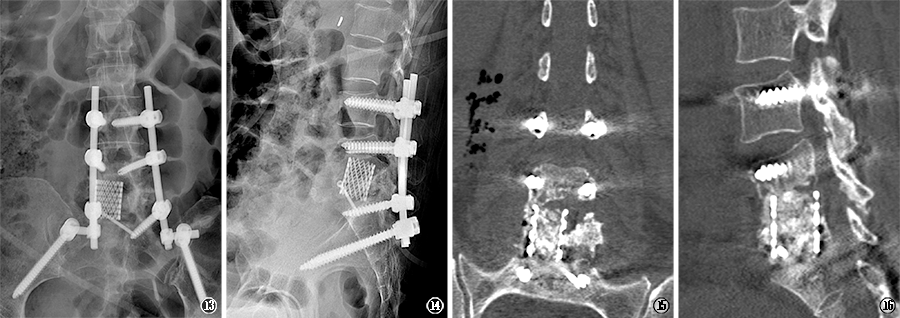

图13,14

2022年1月7日,行腰椎X线片,提示第3腰椎至骶椎内钉棒内固定物影及钛合金融合物影;

图15

,16 2022年1月7日,腰椎CT冠状位及矢状位重建,可见钛合金融合物内植骨影像,腰4,5及腰5-骶1椎间隙狭窄